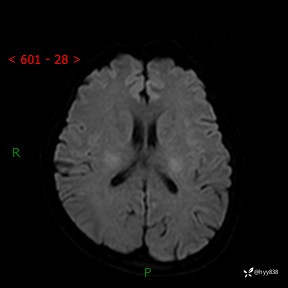

颅脑MRI平扫